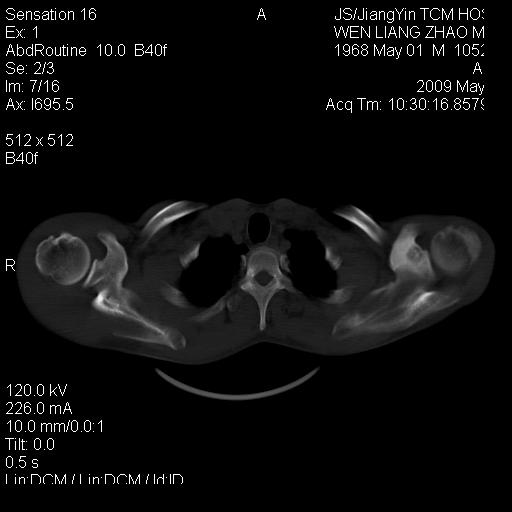

标题: CT19762:左侧喙突处压痛二年。考虑骨样骨瘤。 [打印本页]

标题: CT19762:左侧喙突处压痛二年。考虑骨样骨瘤。

左侧喙突处压痛二年。考虑骨样骨瘤。

病灶外缘膨胀明显,灶缘硬化较少,结合病史较符合骨母细胞瘤,其他亦不排除如软骨及软骨母细胞瘤等(病灶形态,成份较符合,发病部位也符合,只是年龄较大),骨样骨瘤多有较明显的自发性痛,且夜间痛明显,病史为压痛两年,不太符合.

多考虑内生性软骨瘤。年龄及发病部位及病史不支持骨样骨瘤。

首先考虑内生软骨瘤,其次才考虑骨样骨瘤。